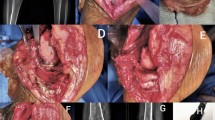

This study was conducted to examine the long-term survivorship and functional outcome of distal femoral varus osteotomy with fresh osteochondral allograft following failed lateral tibial plateau fracture surgery. We hypothesized that this procedure would be associated with a low rate of conversion to total knee arthroplasty (TKA) at medium to long-term follow-up.

A consecutive series of 27 of distal femoral varus osteotomy combined with fresh osteochondral allograft following (27 patients) conducted between January 1981 and January 2005 for failed lateral tibial plateau fracture was retrospectively reviewed. Outcome measures included the Knee Society Knee Score (KSKS) and Knee Society Function Score (KSFS) and conversion rates to TKA.

The study group consisted of 15 females (55.6 %) and 12 males (44.4 %), with a median age of 41.2 years (range 17–62 years). The median follow-up was 13.3 years (range 2–31 years). The knee function scores improved significantly at 2 years post-surgery (p < 0.01) from a median of 54.6 points preoperatively to 83.8 points (KSKS) and median of 50.6 points to 71.1 points (KSFS) at 2 years post-distal femoral varus osteotomy with fresh osteochondral allograft following surgery. At most recent follow-up, 4/27 patients had required conversion to TKA, and one patient had fractured the FOCA, requiring revision of the allograft. The survivorship for distal femoral varus osteotomy with fresh osteochondral allograft following was 88.9 ± 4.6 % at 10 years, 71.4 ± 18.1 % at 15 years, and 23.8 ± 11.1 % at 20 years.